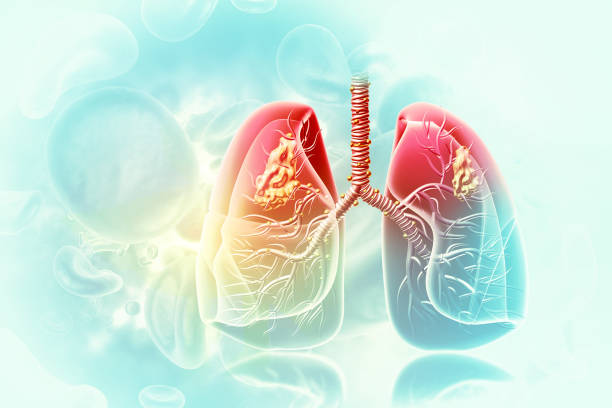

폐암 원인

폐암 원인은 다양하지만 유전적 요인, 환경적 요인, 흡연 등이 있는 것으로 알려져 있으며 가족력이 특히 중요해 가족력이 있는 경우 꾸준한 관리가 중요합니다. 또한, 폐암의 대표적인 병인으로서 흡연은 직간접적인 영향이 강하여 폐암의 병인과 떼려야 뗄 수 없는 중요한 것으로 여겨집니다.